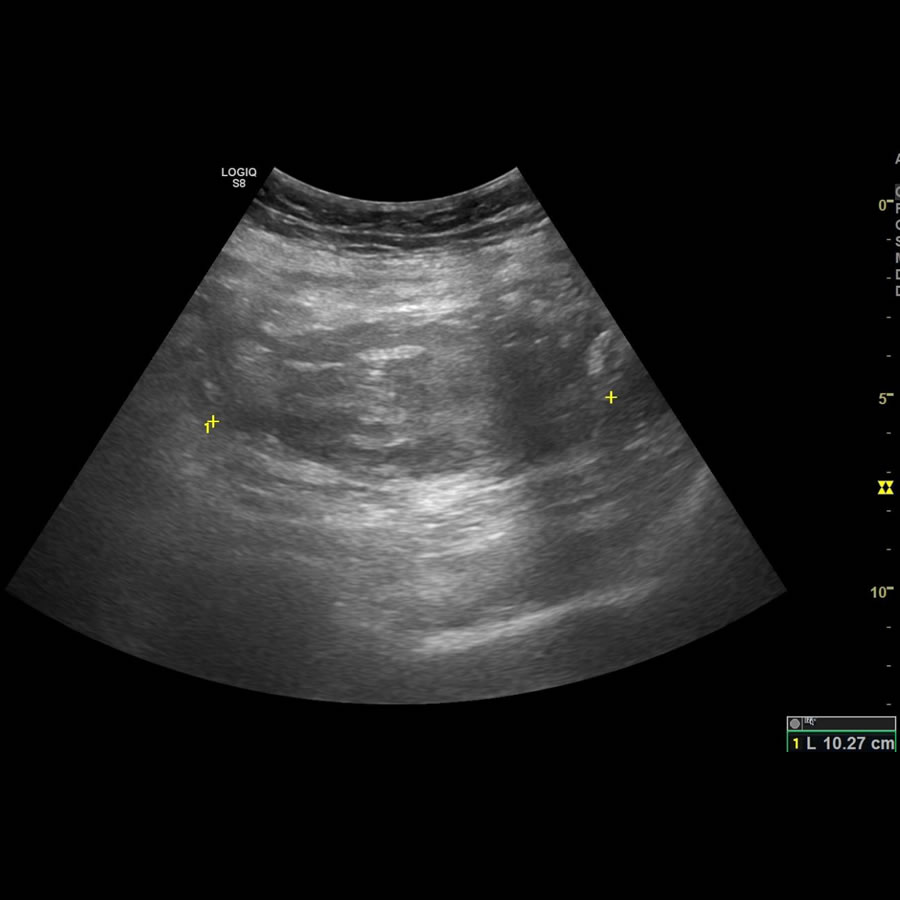

Paciente femenina de 64 años.

Lipotimia. Hipotensión sostenida.